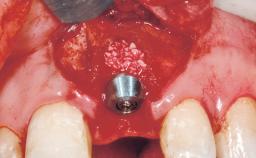

Placement Protocol | Immediate implant placement |

Socket Morphology | Single-root socket |

Socket Integrity | Sufficient, with intact bone walls |

Bone Volume | Sufficient, with intact walls |